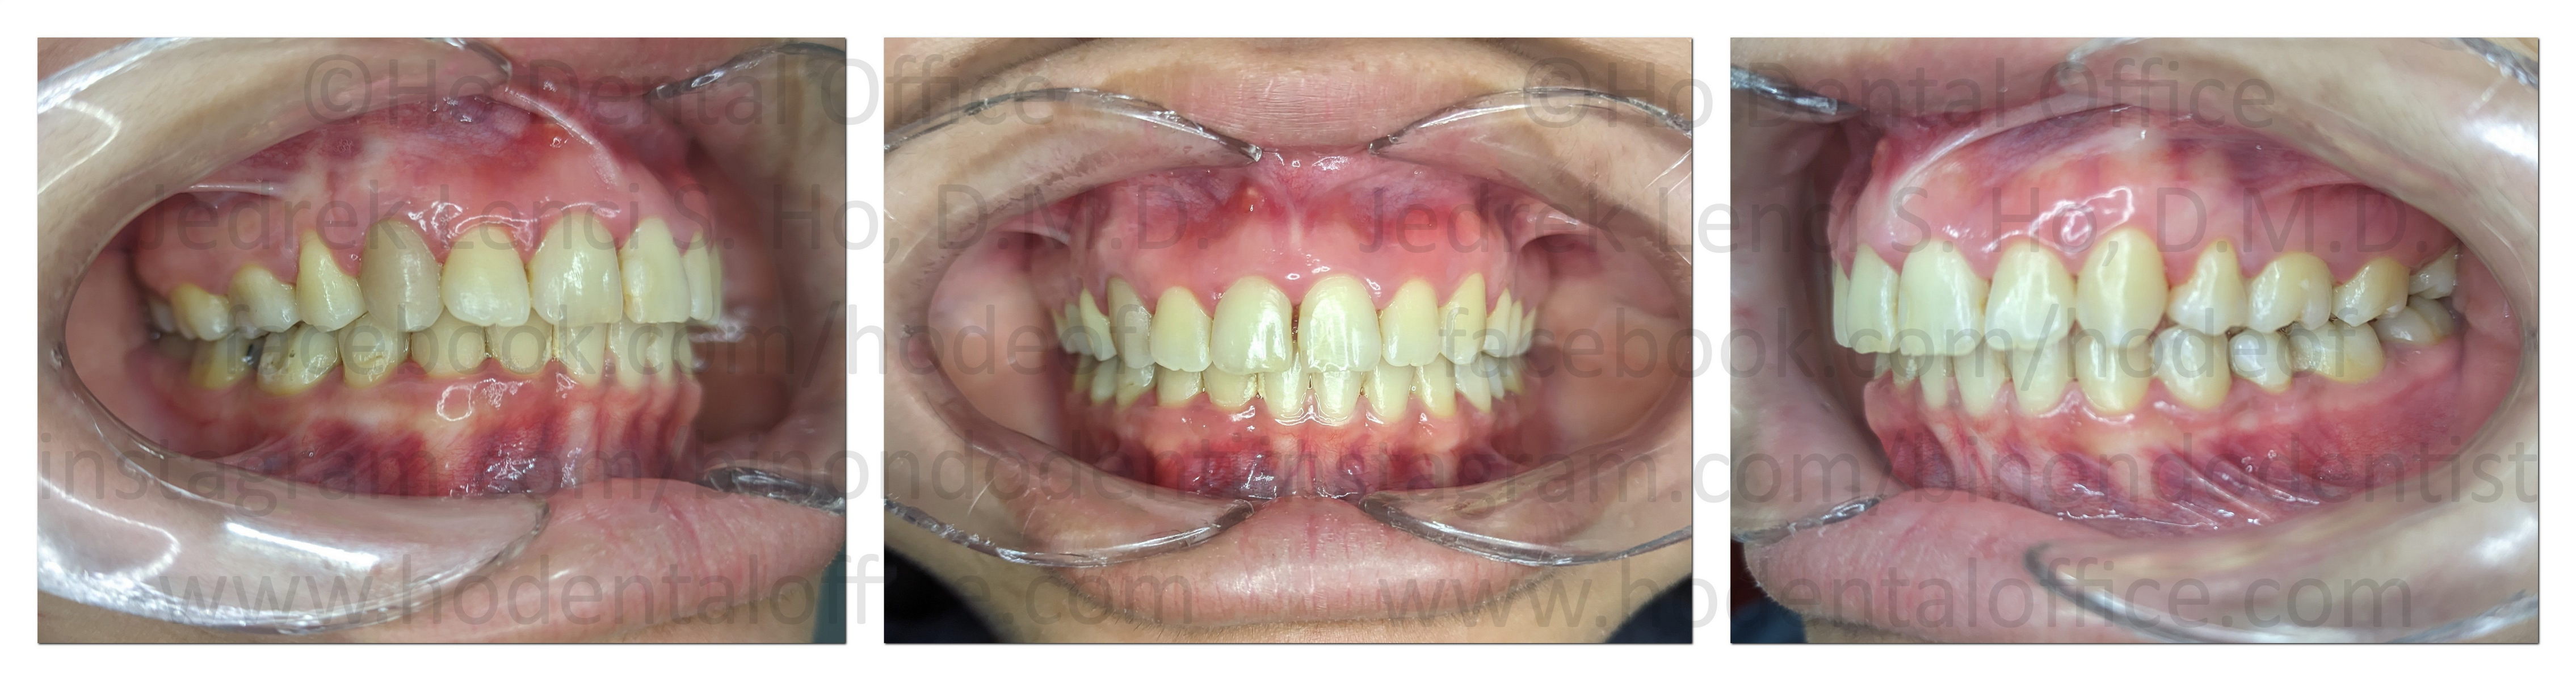

This is the patient 3 years after her gingivectomy. The gums remain healthy and the gingival enlargement has not relapsed.